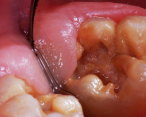

A 9-year-old boy had a partially erupted mandibular first molar with much hypocalcification of the occlusal surface and a large caries lesion involving the occlusal and buccal surfaces (Figure 1). The patient complained of continuing sensitivity to cold stimulus and air inspiration. Because the tooth was only partially erupted, consideration for stainless steel crown full coverage had to be delayed. As an interim repair, it was decided to debride the carious tooth substance and place a light-hardened calcium silicate/mineral trioxide aggregate (MTA) liner, followed by a bonded restoration. After inferior alveolar block anesthetic injection and cotton roll isolation, cavity outline form was cut using a high-speed, water-cooled, medium-grit cylindrical diamond bur (Figure 2). Insufficient eruption precluded use of a rubber dam. A large, round bur at slow speed was used to debride the carious enamel and dentin. The prepared surfaces were swabbed for two 60-second applications of a 5% glutaraldehyde/HEMA solution for desensitization and disinfection of the preparation.6,7 Cavity liner was then injected and spread over the deepest sections of the cavity floor and hardened with the visible light beam (Figure 3). After a self-etching bonding agent was applied over the remaining enamel surfaces, without the need for any type of matrix, an RMGI bioactive ionic resin-based composite was injected, in one portion, into the preparation and spread over the four cusps using a ball burnisher. This restorative complex was then photo-polymerized using two 20-second exposures of the visible light beam (1,200 mW/cm2). The restoration was trimmed and finished with large, round diamond burs at slow speed, and occlusion was evaluated with articulating paper and adjusted.

The tooth was prepared for interim sedative restoration.

Figure 2

Cavity liner was placed and light-hardened.

Figure 3